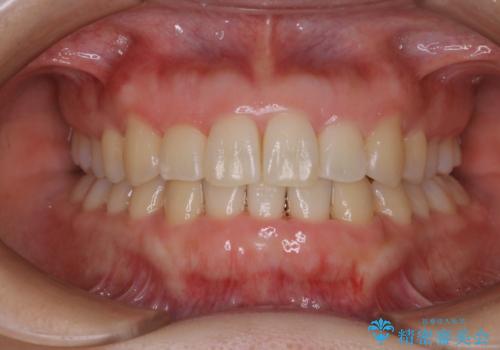

前歯の反対咬合、奥に引っ込んでしまっている歯をインビザラインで治療する

上の前歯の反対咬合があり、治療の途中で下の前歯を乗り越える必要があります。

前歯を乗り越える治療はワイヤーの方が有利ではありますが、インビザライン単独でも行うことができます。